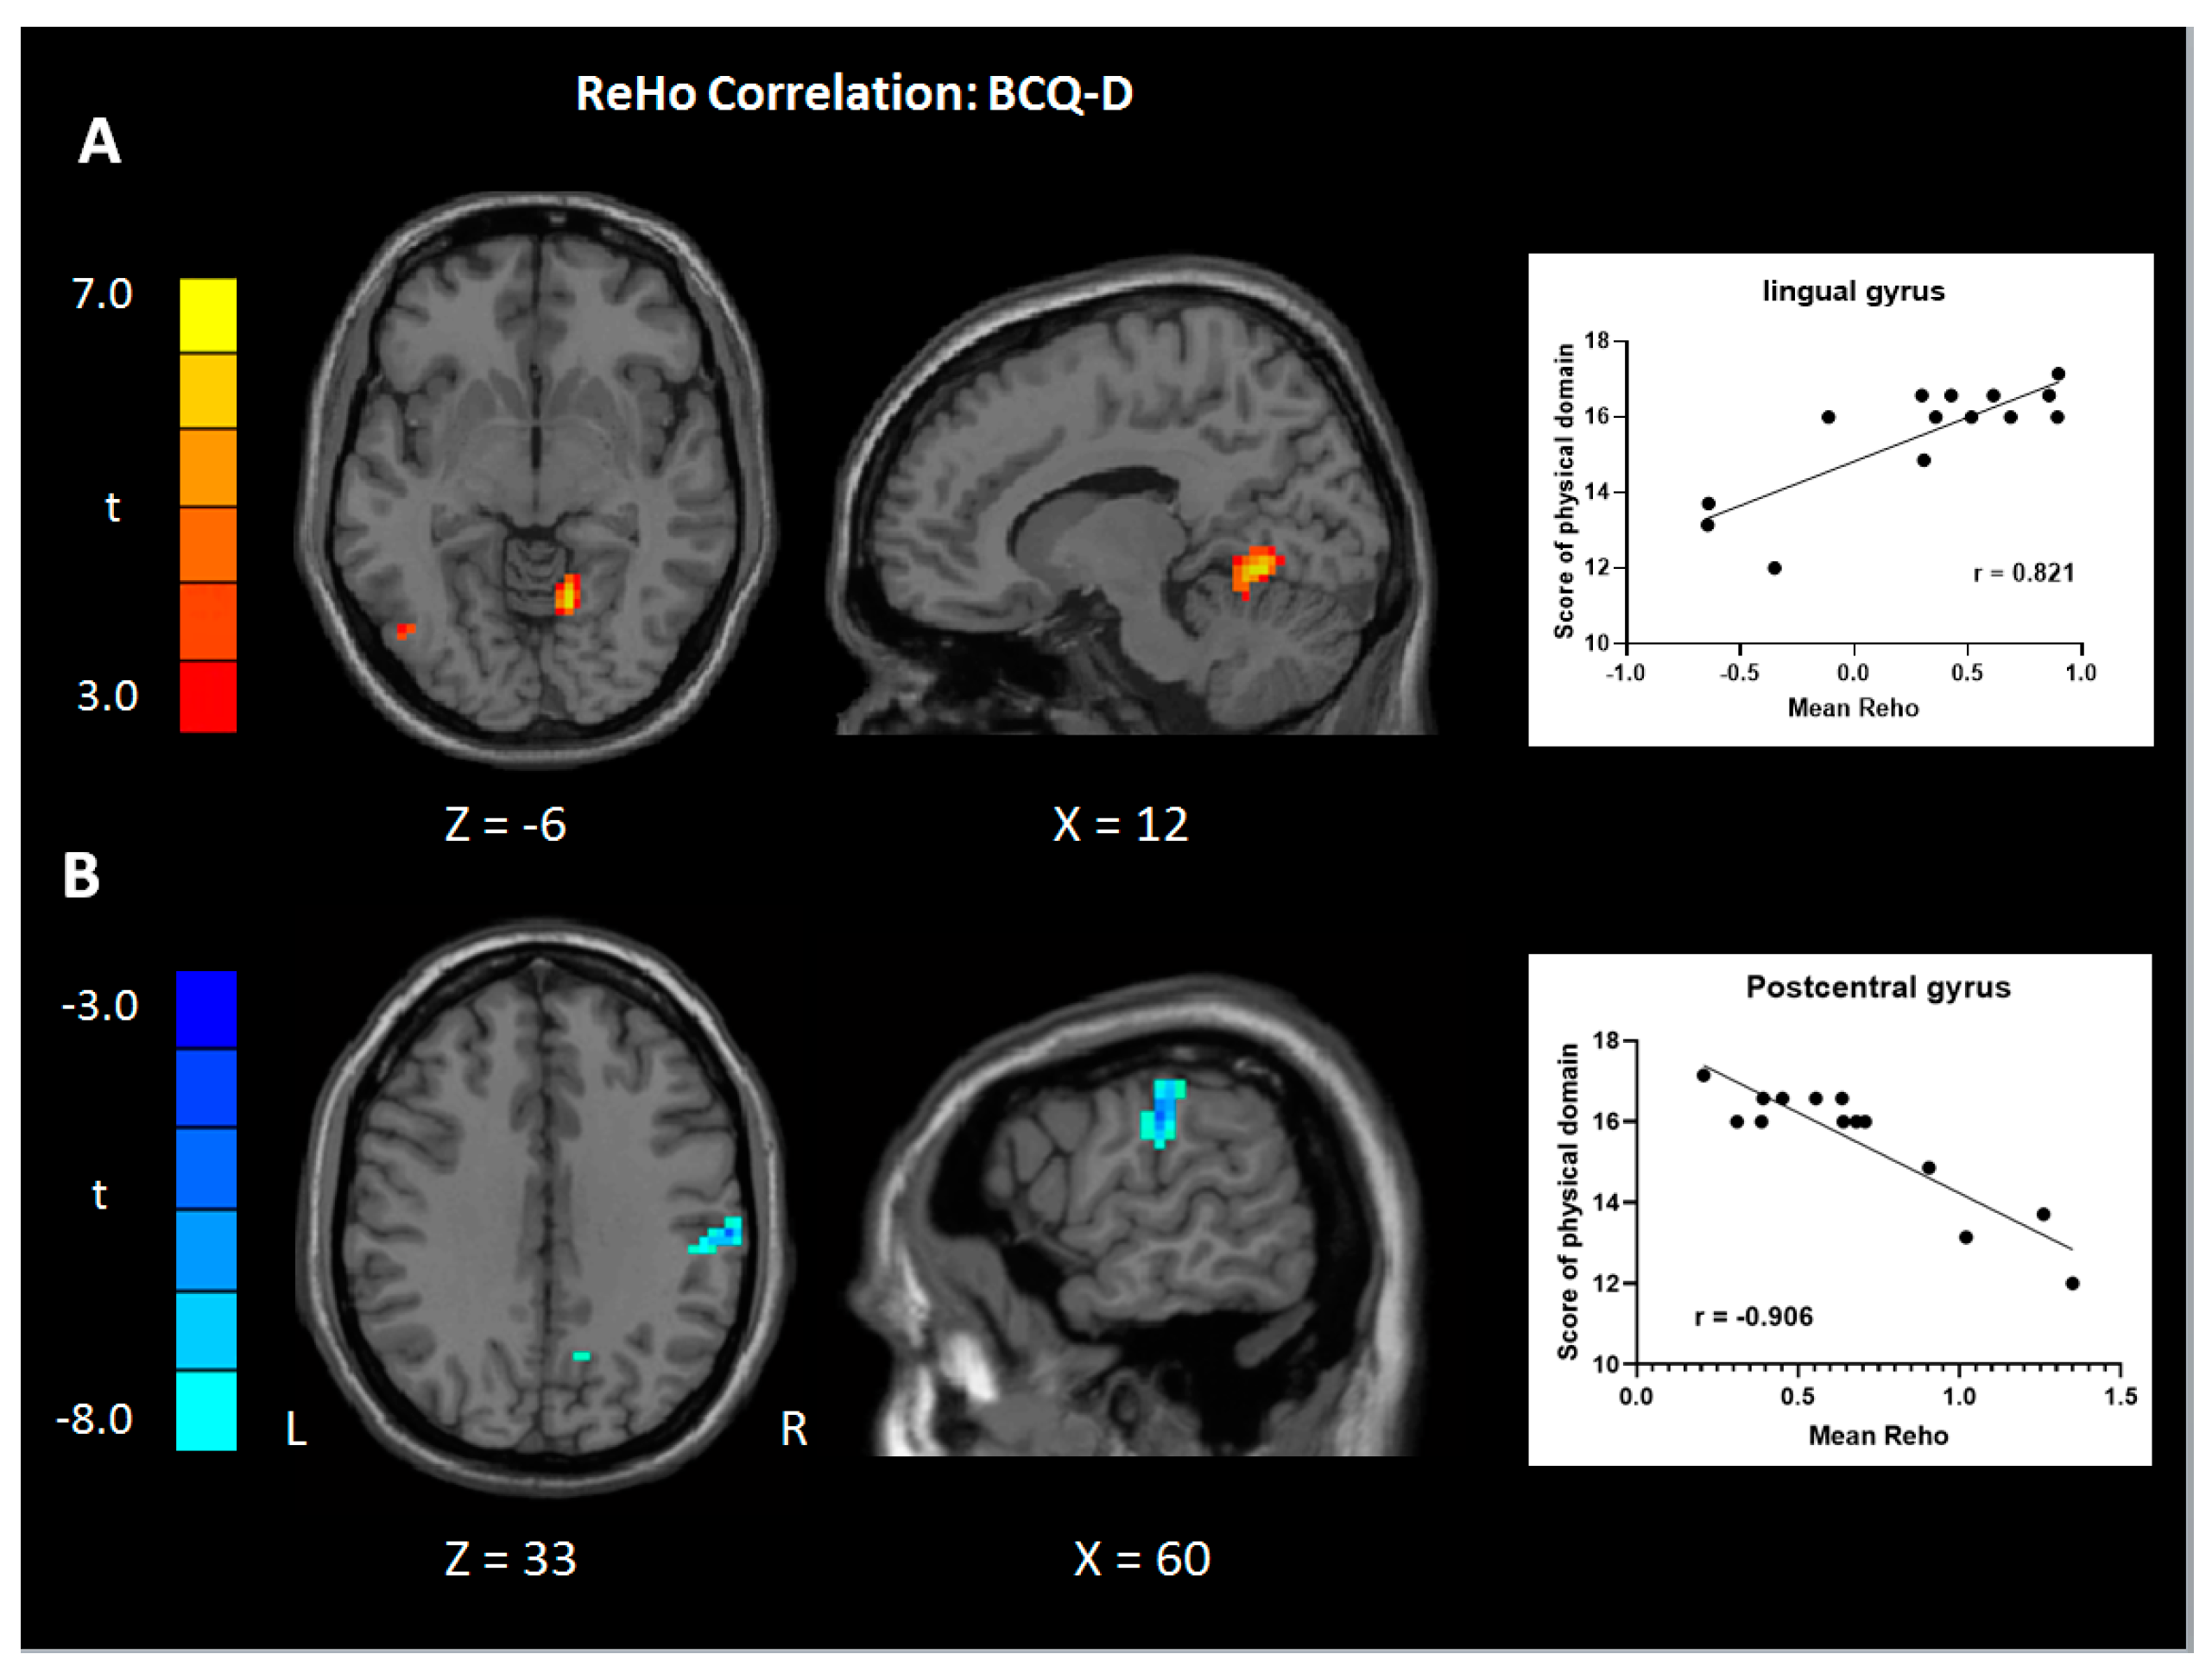

3.4. Correlation Analysis

| Values | Region | BA | Size | t | Peak Coordinate | ||

|---|---|---|---|---|---|---|---|

| x | y | z | |||||

| WHOQOL-BREF | |||||||

| ReHo | |||||||

| Physiological | |||||||

| Positive | Cerebellum/lingual gyrus, R | 19 | 77 | 6.99 | 12 | −57 | −6 |

| Negative | Supramarginal gyrus, R | 40 | 68 | 8.58 | 60 | −21 | 33 |